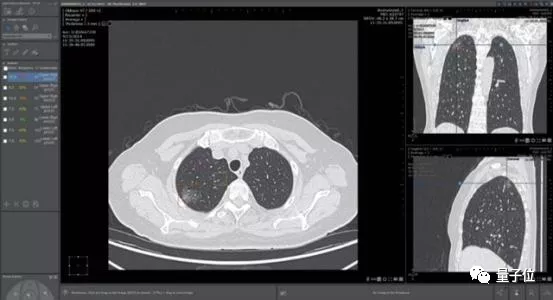

除了之前提到的临床应用Streams,他们还开发了可以筛查乳腺癌和识别50多种眼疾的技术。

除了饱受争议的Streams应用,谷歌健康成立后重点宣传的糖尿病视网膜病变筛查业务,也在落地上出现了不少问题。

据谷歌发表在《美国医学会期刊》(JAMA)上的研究显示,AI算法在这一研究中起到的作用极大,使得这一工具的准确率达到了90%,理论上几秒就能出结果,“足以和眼科专家的诊断结果相媲美”。

医疗影像辅助诊断是当时医疗AI公司扎堆投入的领域。这家公司最大的卖点肺结节诊断,则是红海中的红海。

一家医院接入4、5家AI肺结节诊断产品成了司空见惯,曾有影像医师笑称:

中国人的肺结节都不够用了。